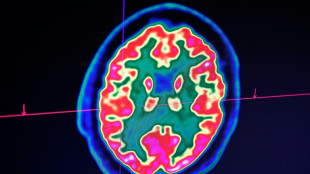

Le système immunitaire impliqué dans les dégâts cérébraux liés au Covid-19 (étude)

La réponse immunitaire au Covid-19, qui abîme les vaisseaux sanguins du cerveau, pourrait être responsable des symptômes du "Covid long", selon une étude basée sur un faible nombre de cas et publiée mardi par des chercheurs américains.